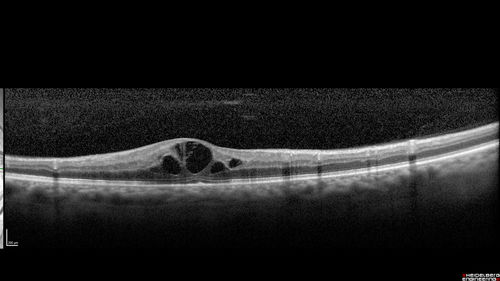

Diabetic Macular Edema - One eye treated with Eylea and 2 weeks later both were improved

68 year old female with diabetic retinopathy and macular edema

VA OD: sc20/40 PH20/32

VA OS: sc20/40 PH20/32

IOP: TP: OD:14 OS:14 Time:12:45

Diabetic Macular Edema - Fellow eye reponded to Eylea